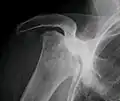

Radiography of total avascular necrosis of right humeral head. Woman of 81 years with diabetes of long evolution.